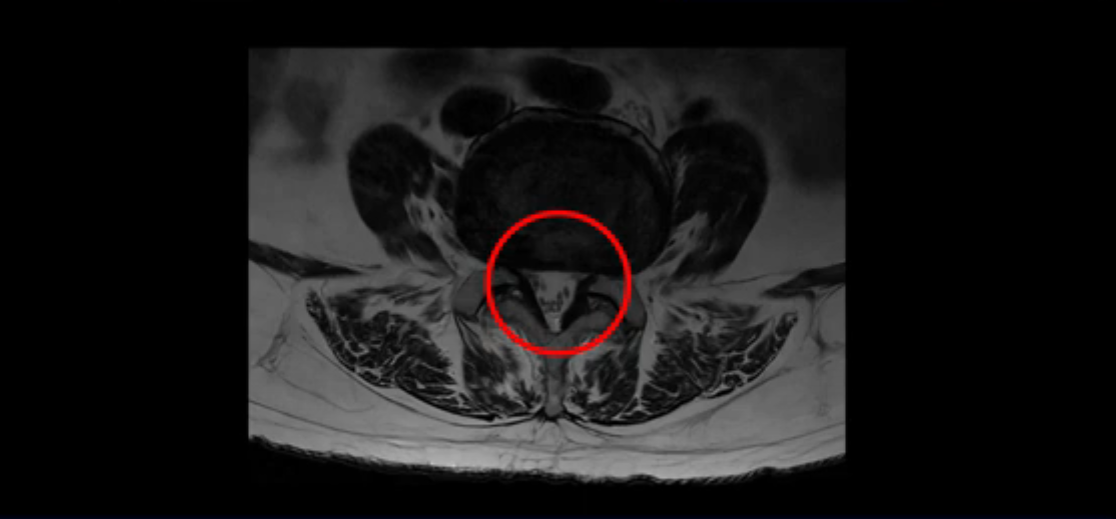

척추관도 좁아져 있습니다.

이렇게 신경 구멍들이 좁아져 있어서 신경눌림 증상이 엉덩이와 다리에 생기는데, 이런 증상들은 근육과 매우 밀접한 관련이 있습니다.

협착증 환자분들 중 걸을 때만 다리가 저리고 아픈 분들이 있고, 반면에 앉거나 누울 때도 허리, 엉덩이, 다리가 아프고 저린 분들이 있습니다. 이 환자분처럼 앉아도 누워도 아픈 분들일수록 근육 문제가 심한 분들이고, 이런 분들은 걸을 때만 아픈 분들에 비해 수술 결과도 더 안 좋고 따라서 수술 이후에도 아플 가능성이 높습니다. 꼭 알아두시길 바랍니다. 저희 모커리한방병원에서는 걸을 때만 다리가 저리고 아픈 분들을 단순형 협착증, 걸을 때 말고도 앉거나 누울 때도 허리, 엉덩이와 다리가 저리고 아픈 분들을 복합형 협착증이라고 부르는데, 이 환자분이 바로 복합형 협착증 환자분입니다.